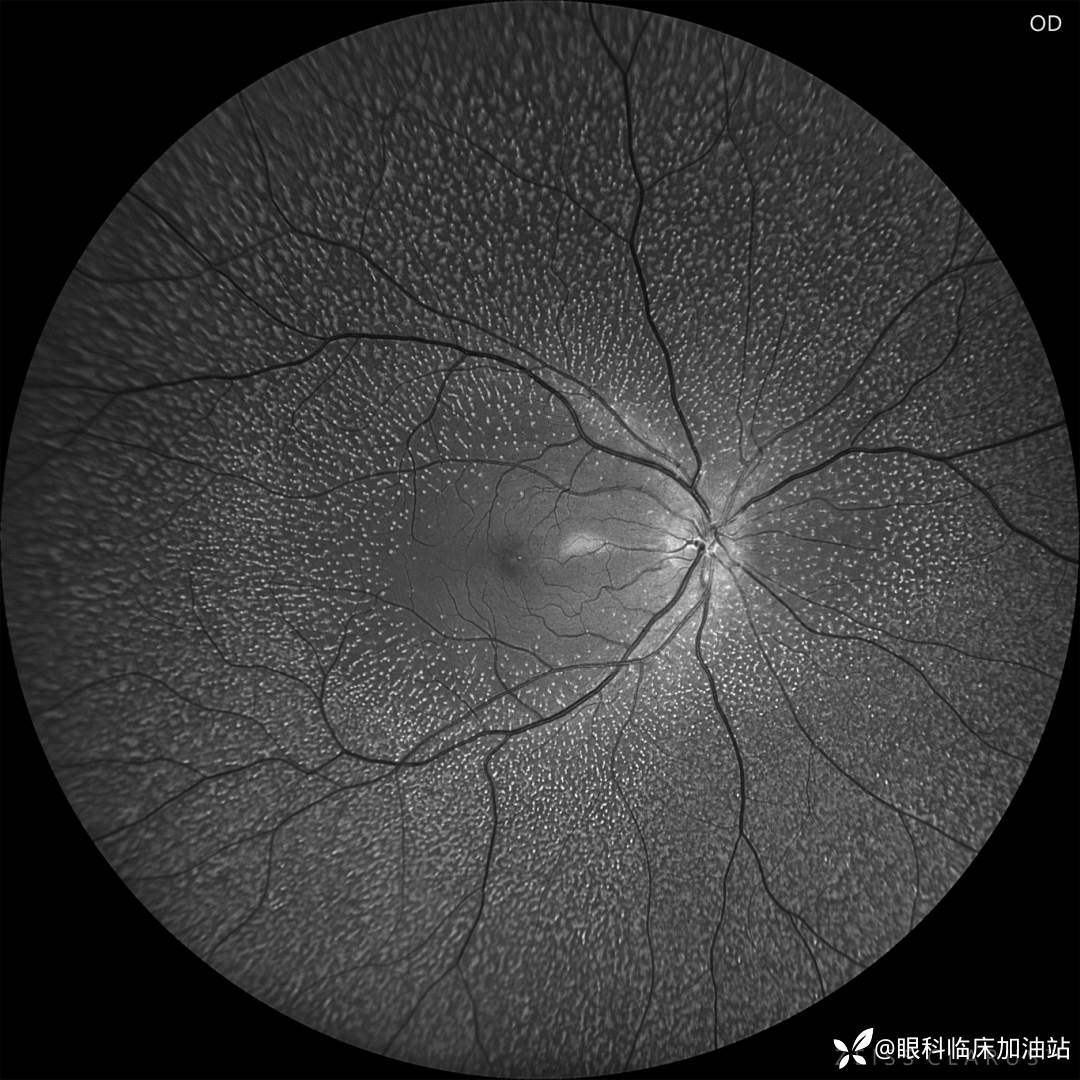

眼底照相

右眼